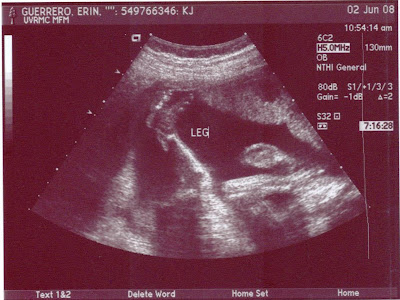

Here is the missing picture. When I scanned Little Gabriel's pictures I accidentally forgot to add this one. You can see his little hand really close to his face. We really wanted him to look at us, but he didn't. I guess he is already trying to rebel against his authority figures ;0)